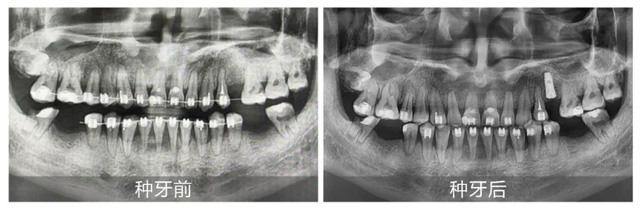

劉先生術(shù)前術(shù)后全景片對(duì)比